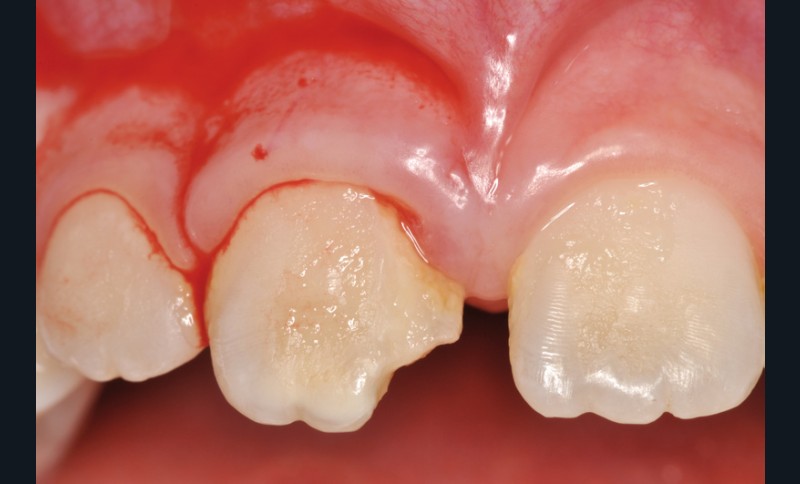

a à d Jeune patiente âgée de 8 ans, adressée suite à un traumatisme survenu 3 semaines auparavant, pour l’extraction de sa 21. La vue clinique montre un saignement ligamentaire, une mobilité coronaire et une fracture coronaire amélodentinaire longitudinale partant de l’angle mésial et se poursuivant en direction radiculaire sous-gingivale (a). Un test de vitalité positif indique que la dent est vitale, la radiographie permet de poser le diagnostic de fracture coronoradiculaire, et d’objectiver l’immaturité radiculaire (stade 8 de Nolla) (b). Une contention est mise en place et la plaie dentinaire coronaire est scellée au mieux par collage afin de limiter le risque d’une complication infectieuse (c). A 15 jours la dent est vivante et aucune complication n’est apparue (d). La patiente est revue après 3 mois pour déposer la contention, le test de vitalité est positif, et la radiographie de contrôle montre une apexogenèse en cours (e). Cependant la gencive s’est invaginée dans le trait de fracture (f). La zone est débridée sous microscope (g) puis scellée et reconstituée à l’aide d’un adhésif SAM et d’un composite fluide (h). Le contrôle radiographique à 6 mois est satisfaisant (i). Ce cas clinique illustre le fort potentiel des pulpes jeunes et du ligament alvéolodentaire à résister aux agressions et à assurer les fonctions dentinogénétiques et l’édification radiculaire.